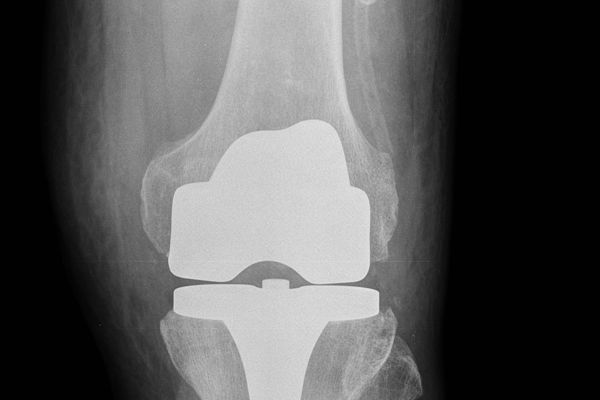

Gabinet ortopedyczny prowadzony przeze mnie specjalizuje się w leczeniu schorzeń i urazów kończyn górnych i dolnych. Zajmuję się leczeniem choroby zwyrodnieniowej stawu biodrowego i kolanowego, uszkodzeń wewnętrznych stawu kolanowego i barkowego, złamań w obrębie kończyn górnych i dolnych oraz urazów ścięgien i mięśni kończyn górnych i dolnych. Ponadto wykonuję diagnostykę USG narządu ruchu i badanie preluksacyjne (USG bioderek niemowląt). Leczę również neuropatie uciskowe kończyn (zespół kanału nadgarstka, rowka nerwu łokciowego, kanału Guyona) oraz uszkodzenia wewnętrzne stawów kończyn górnych i dolnych. Zapraszam do mojego gabinetu, gdzie dobiorę odpowiednie do schorzenia metody leczenia i zakwalifikuję do ewentualnego leczenia operacyjnego. W celu umówienia się na wizytę proszę o kontakt telefoniczny z rejestracją gabinetu ortopedycznego w Lesznie.